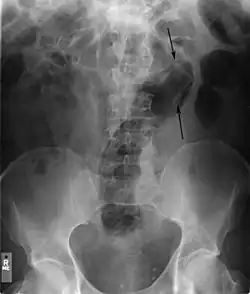

Vor dem Entfernen des Fremdkörpers werden meist radiologische Bilder in unterschiedlichen Projektionsebenen aufgenommen, um die genaue Lage und Tiefe des Fremdkörpers festzustellen. Dies geschieht in der Regel durch Röntgen. Bei Fremdkörpern aus Materialien, die einen zu geringen Kontrast im Röntgenbild liefern (beispielsweise Gegenstände aus massivem Kunststoff), kann gegebenenfalls auf Sonografie (Ultraschall) oder Computertomographie ausgewichen werden.[24] Die Magnetresonanztomographie ist insbesondere bei unbekannten Fremdkörpern kontraindiziert. In das Rektum eingeführte Fremdkörper können unter Umständen bis weit in das Kolon vordringen, in einigen Fällen bis zur rechten Flexur.[11]